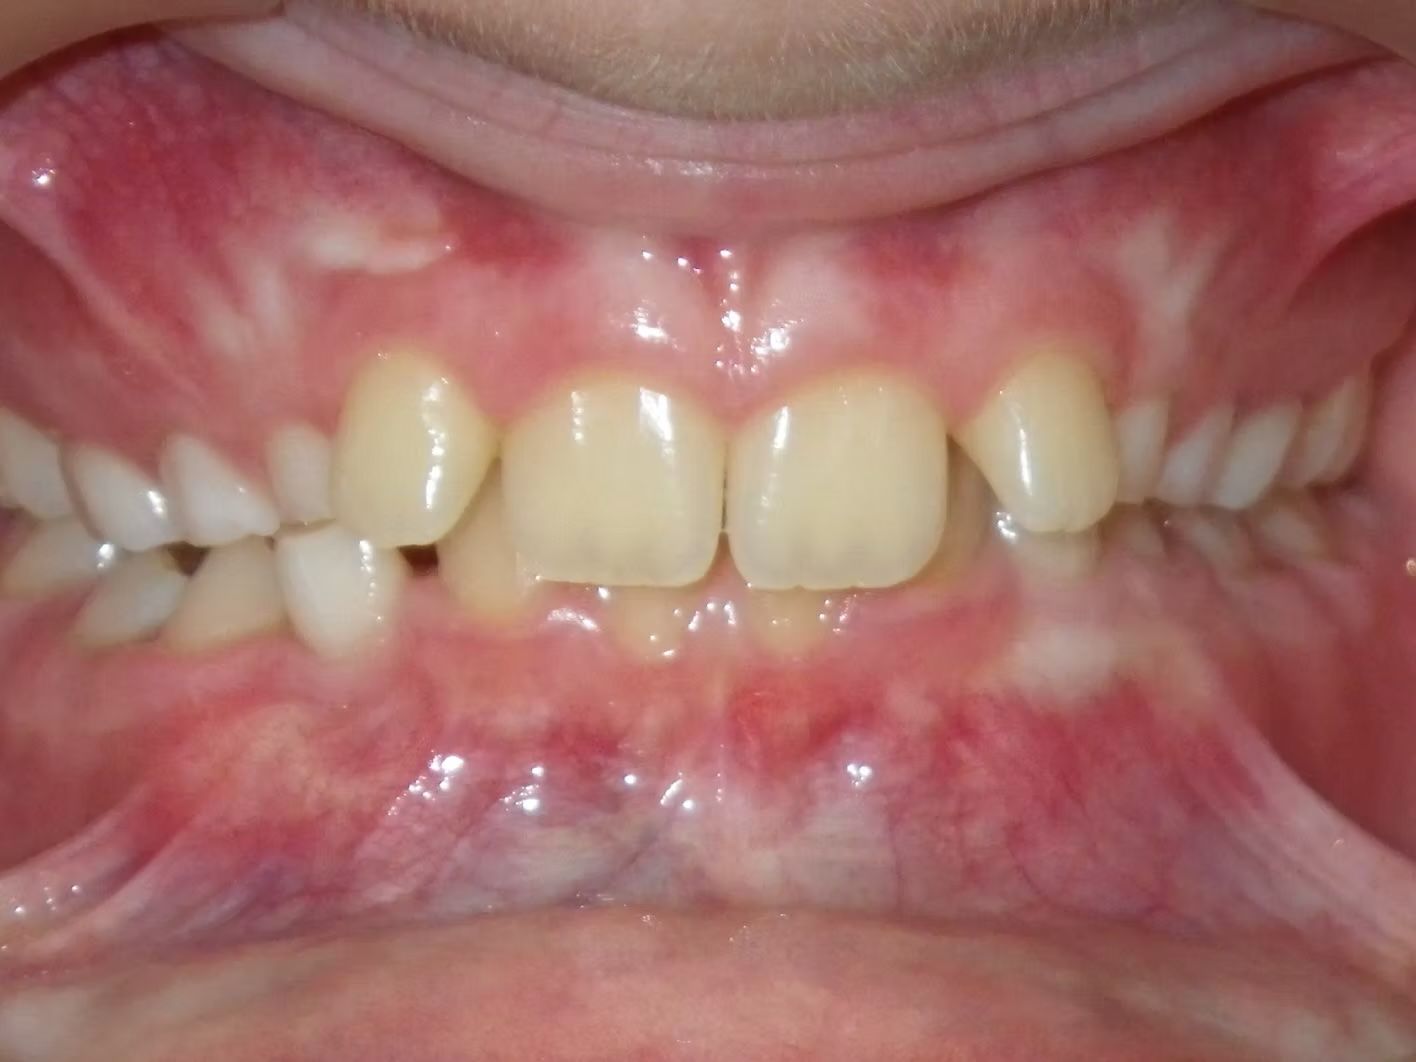

AUSTIN

Austin didn't like that his upper teeth fit behind his lower teeth. (He had an anterior crossbite). When this happens there are usually 3 ways to correct it. One way is just to move the top teeth forward, another is to take out teeth to help correct the crossbite, and sometimes and thankfully less common is to have jaw surgery to correct a skeletal size discrepancy between the top and bottom jaw. Dr. Bret was able to align Austin's teeth and correct his cross bite without taking out any teeth. Austin was super happy and loves his new smile.